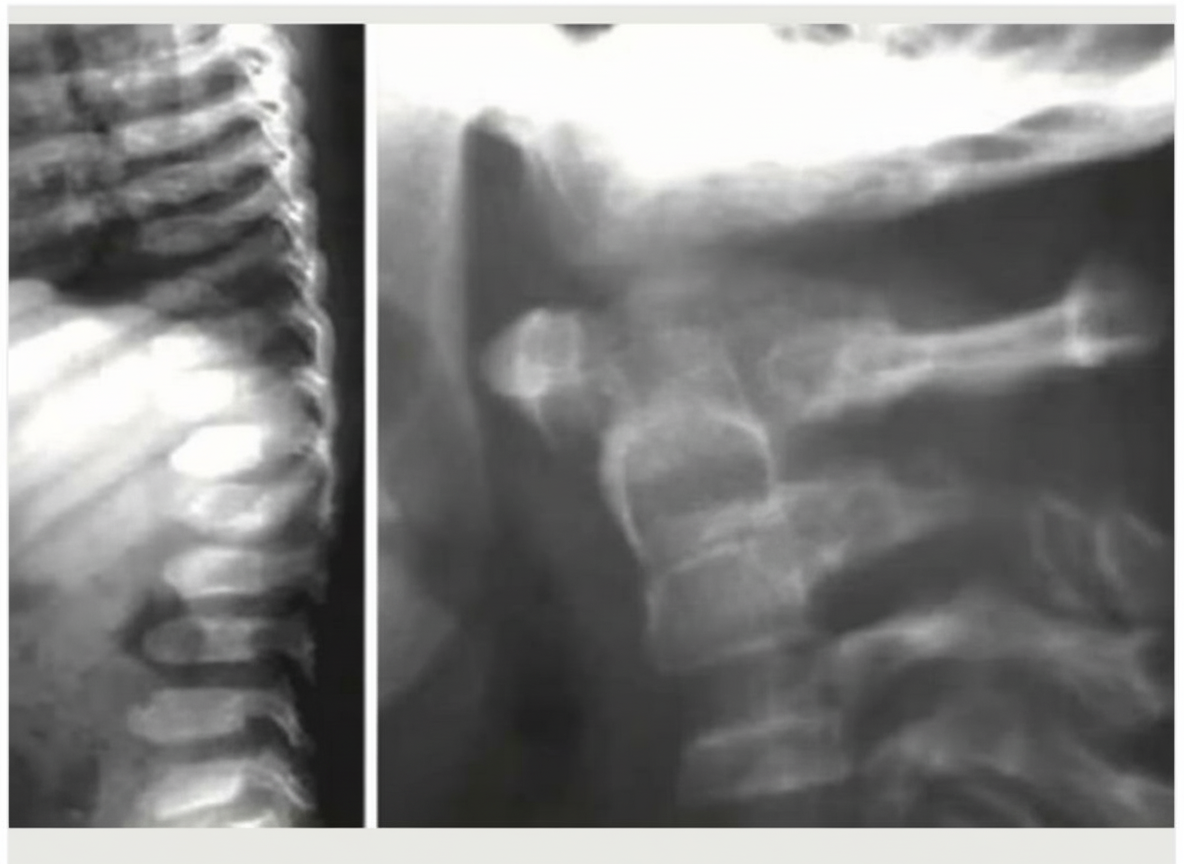

In which of the following diseases are the given X-ray findings typically seen?

Explanation: ***Morquio disease*** - Classic **skeletal dysplasia** findings include **platyspondyly** (flattened vertebrae), **odontoid hypoplasia**, and **genu valgum** (knock-knees). - Additional X-ray features show **flared iliac wings**, **epiphyseal dysplasia**, and **short stature** with disproportionate limbs. *Gaucher disease* - Primarily shows **Erlenmeyer flask deformity** of distal femur and **bone infarcts** rather than skeletal dysplasia. - **Hepatosplenomegaly** is prominent, but characteristic skeletal malformations of mucopolysaccharidoses are absent. *Fabry disease* - **X-ray findings are typically normal** as this lysosomal storage disease primarily affects cardiovascular and renal systems. - Clinical features include **angiokeratomas** and **corneal deposits**, not skeletal abnormalities. *Niemann Pick disease* - **Skeletal involvement is minimal** with normal bone architecture on X-rays. - Disease primarily causes **hepatosplenomegaly** and **cherry-red spot** on fundoscopy, not bone dysplasia.